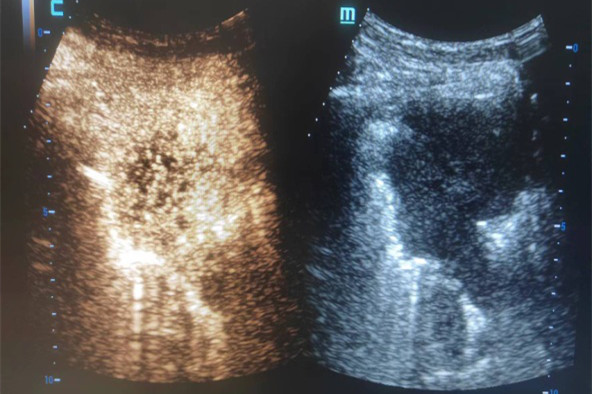

超声造影作为超声检查的一种新型检查方式,是通过观察组织的微灌注情况来判断肿块的良恶性,目前广泛应用于腹腔各脏器肿瘤及甲状腺、乳腺等浅表肿瘤的检查。穿刺术中的超声造影,可以显示肿块内及周边的血管分布情况,区分肿块组织的活性区域,有效指引操作者避开穿刺路径上的大血管和病灶内坏死区域,提高穿刺活检的成功率,减少并发症的发生。相对于传统的X线引导下穿刺活检,具有无放射性、实时、精准、全程显示穿刺针道、安全、高效等优势。